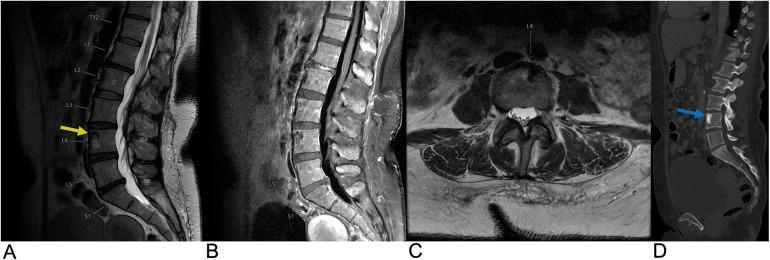

Spinal lesions encompass a diverse range of pathologies, including primary and secondary tumors, infectious processes, vascular malformations, traumatic injuries, and degenerative conditions, each with distinct imaging characteristics crucial for accurate diagnosis and management. Imaging plays vital roles in assessing lesion morphology, anatomical localization, and neurological impact, guiding clinical decision-making and therapeutic planning. This review systematically explores spinal lesions based on their anatomical compartments, highlighting key radiological features and providing a comprehensive reference for radiologists.

脊柱病变包括多种病理情况,包括原发性和继发性肿瘤、感染性病变、血管畸形、创伤性损伤以及退行性疾病,每种病变都具有独特的影像学特征,这些特征对于准确诊断和治疗至关重要。影像学在评估病变形态、解剖定位和神经影响方面发挥着至关重要的作用,指导临床决策和治疗规划。本综述基于解剖分区系统地探讨脊柱病变,突出关键的放射学特征,并为放射科医生提供全面的参考。